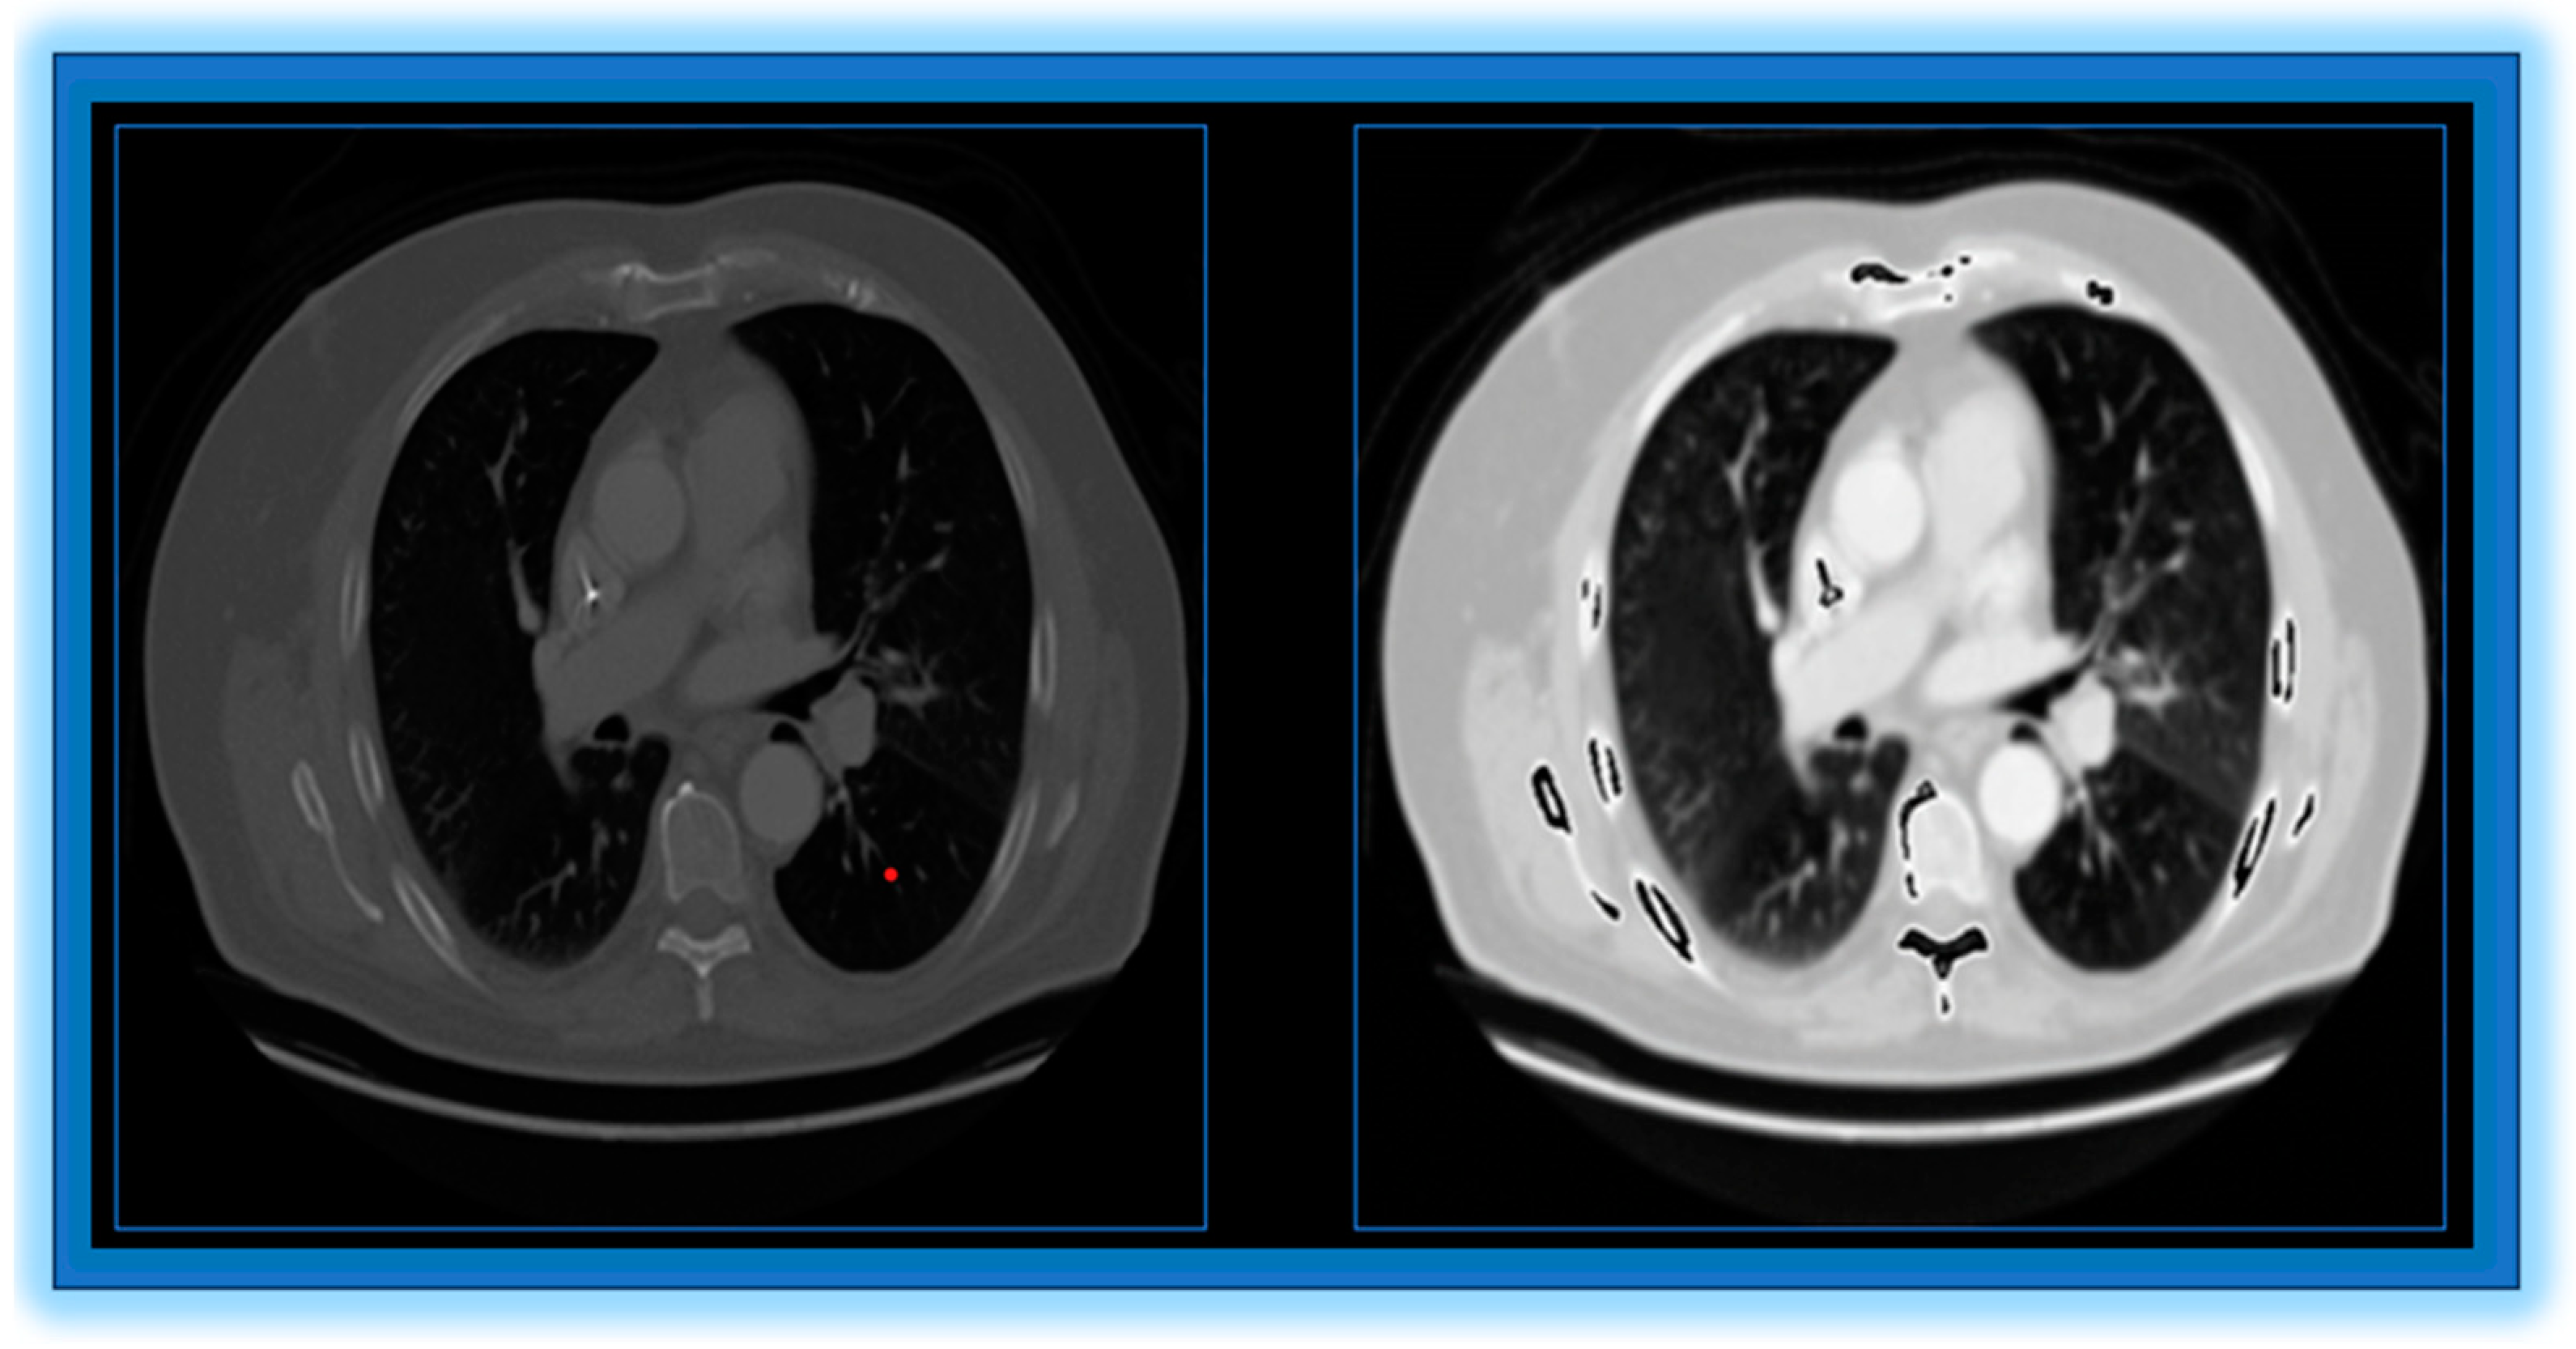

- The quality of CT images affects the accuracy of the classification process.

- Preprocessing: To enhance image quality and make additional analysis easier, lung computed tomography images are first preprocessed. This involves multiple steps.

- Noise Reduction: We remove noise from CT images by applying a sophisticated improved anisotropic diffusion filter (I-ADF) approach.

- Contrast stretching: Enhancing the contrast of the images makes important features more distinguishable.

- Convex Hull Lung Region Extraction: In order to concentrate the analysis on the pertinent area, we isolate the lung region.

- Edge Enhancement: Using the unsharp masking filter (UMF) improves the ability to define the image edges.